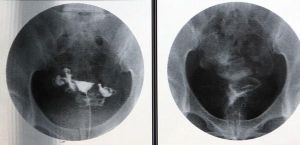

如何治療僵直性脊柱炎:

1.減輕疼痛

2.保持脊椎活動範圍及功能

3.並預防併發症的發生。